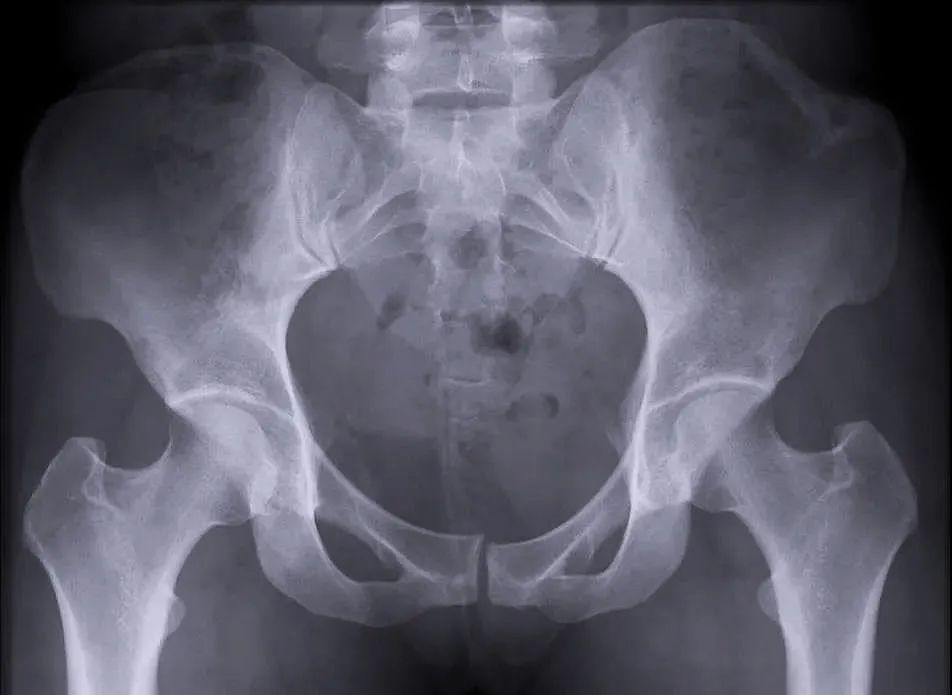

【医疗科普】:外伤性骨折影像

外伤性骨折

一、外伤性骨折&病理性骨折

我们通?;岚压桥韫钦鄯治馍诵缘墓钦郏ㄒ簿褪潜┝π缘墓钦郏┖筒±硇缘墓钦?。暴力性骨折多是由外伤引起的,病理性的骨折有可能是病人患有某些疾病,比如肿瘤、骨质疏松等引起的一些在外力较小的情况下发生的骨折,这叫“病理性的骨折”。